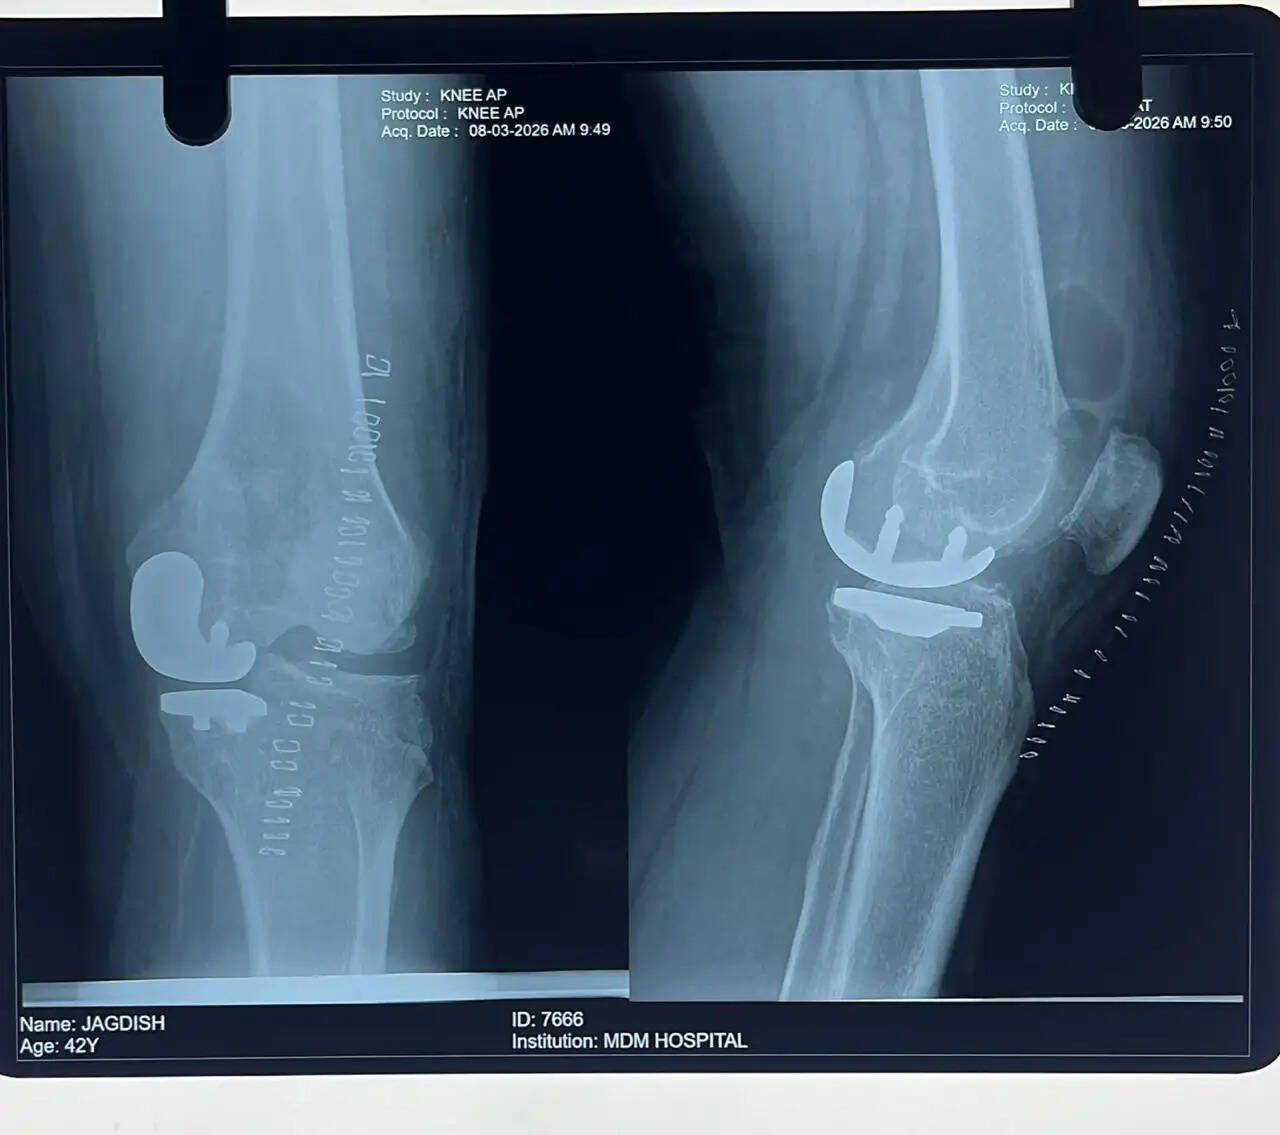

अस्थि रोग विभाग के विभागाध्यक्ष डॉ. अरुण वैश्य ने बताया कि एक मरीज घुटने में दर्द की समस्या लेकर अस्पताल आया था। जांच के दौरान पाया गया कि घुटने के जोड़ के तीन हिस्सों में से केवल एक हिस्सा (मीडियल टिबियो-फेमोरल भाग) में आर्थराइटिस था, जबकि बाकी दो हिस्से सामान्य स्थिति में थे। मरीज की कम उम्र और घुटने के लिगामेंट्स की अच्छी स्थिति को देखते हुए पूरे घुटने को बदलने के बजाय केवल प्रभावित हिस्से का ही रिप्लेसमेंट करने का निर्णय लिया गया। इस प्रक्रिया को यूनिकंडाइलर नी रिप्लेसमेंट कहा जाता है।

डॉ. वैश्य ने बताया कि इस तकनीक से मरीज को घुटना लगभग सामान्य जैसा महसूस होता है। साथ ही यह सर्जरी छोटे चीरे से की जाती है, जिसमें रक्तस्राव कम होता है, दर्द कम होता है और ऑपरेशन कम समय में पूरा हो जाता है। ऑपरेशन के बाद मरीज जल्दी चलने-फिरने में सक्षम हो जाता है।